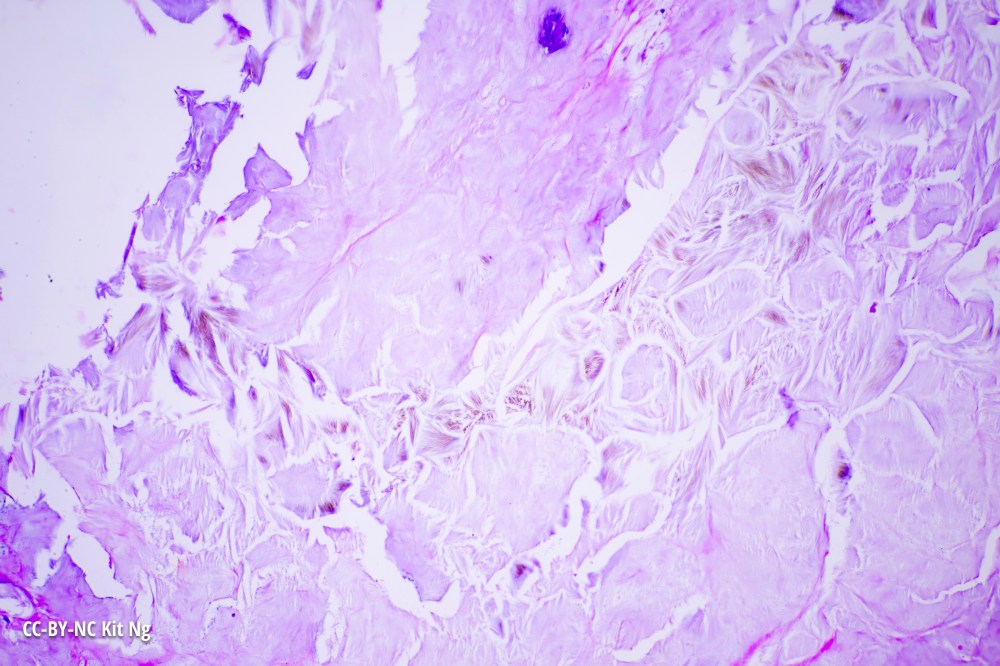

The gout crystals, formed from uric acid, can be seen under human skin in this specimen.